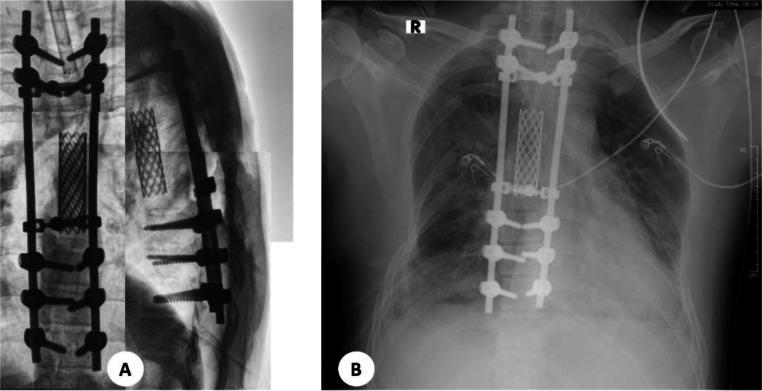

Chondrosarcomas are one of malignant tumors in which cartilaginous matrix is produced. It is divided into 2 groups including primary or secondary. Primary chondrosarcomas are the third most common primary malignant tumors of the bone. Chondrosarcoma represents 20%-27% of all primary malignant bone tumors. Primary spinal chondrosarcoma is exceedingly rare among spinal tumors. A 36-year-old man presented to hospital with the swelling on the back accompanied with pain. Swelling and pain have been felt for approximately 3 years. The symptoms gradually worsened. On thoracolumbal X-ray a lytic sclerotic expansile lesion on the right posterior aspect of thoracal T5-T6. MRI showed the mass infiltrated intradural and intramedullary, reaching up to the level of vertebrae T4-T5. This infiltration resulted in stenosis of the spinal canal, obliterating the ligamentum flavum, supraspinous ligament, and interspinous ligament. Chondrosarcomas are uncommon malignant bone tumours that form cartilage; they rarely involve the spine, while most of them occur in young men. The thoracic spine is most commonly involved, but there is usually a long history of pain and possible neurological symptoms. Imaging techniques, such as conventional examination, CT, and MRI, are very important for diagnosis and classification and show typical bone destruction with matrix mineralization. Imaging revealed a lytic sclerotic lesion at the T5-T6 level. CT scans performed subsequently showed an expansile mass with a typical ``rings and arcs'' appearance of chondrosarcomas. MRI further delineated the extent of the mass and the surrounding tissue infiltration, and confirmation of low-grade chondrosarcoma, grade I was based on histological examination. The most effective treatment has been en bloc resection, and high-dose adjuvant radiotherapy might improve local control and survival rates. Recommended follow-ups are for the purpose of monitoring recurrence. Primary spinal chondrosarcoma is a rare malignant tumor that predominantly affects adolescents. The standard treatment typically involves surgical intervention, often supplemented with adjuvant radiotherapy. Many patients experience considerable improvements in neurological function following treatment. Long-term monitoring and follow-up are crucial for ensuring the best possible outcomes for individuals with primary spinal chondrosarcoma.

软骨肉瘤是产生软骨基质的恶性肿瘤之一。它分为两组,包括原发性或继发性。原发性软骨肉瘤是第三常见的原发性骨恶性肿瘤。软骨肉瘤占所有原发性骨恶性肿瘤的20%-27%。原发性脊柱软骨肉瘤在脊柱肿瘤中极为罕见。一名36岁男性因背部肿胀伴疼痛入院。肿胀和疼痛已持续约3年,症状逐渐加重。胸腰椎X线显示胸段T5-T6右侧后方有一个溶骨性硬化性膨胀性病变。MRI显示肿块浸润硬膜内和髓内,达T4-T5椎体水平。这种浸润导致椎管狭窄,黄韧带、棘上韧带和棘间韧带消失。软骨肉瘤是罕见的形成软骨的恶性骨肿瘤;它们很少累及脊柱,大多数发生在年轻男性中。胸椎最常受累,但通常有长期疼痛史和可能的神经症状。影像学技术,如传统检查、CT和MRI,对诊断和分类非常重要,显示典型的伴有基质矿化的骨质破坏。影像学显示T5-T6水平有一个溶骨性硬化性病变。随后进行的CT扫描显示一个膨胀性肿块,具有软骨肉瘤典型的“环和弧”外观。MRI进一步明确了肿块范围和周围组织浸润情况,并根据组织学检查确诊为低级别软骨肉瘤,I级。最有效的治疗方法是整块切除,高剂量辅助放疗可能会改善局部控制和生存率。推荐的随访是为了监测复发情况。原发性脊柱软骨肉瘤是一种罕见的主要影响青少年的恶性肿瘤。标准治疗通常包括手术干预,常辅以辅助放疗。许多患者在治疗后神经功能有显著改善。长期监测和随访对于确保原发性脊柱软骨肉瘤患者获得最佳预后至关重要。